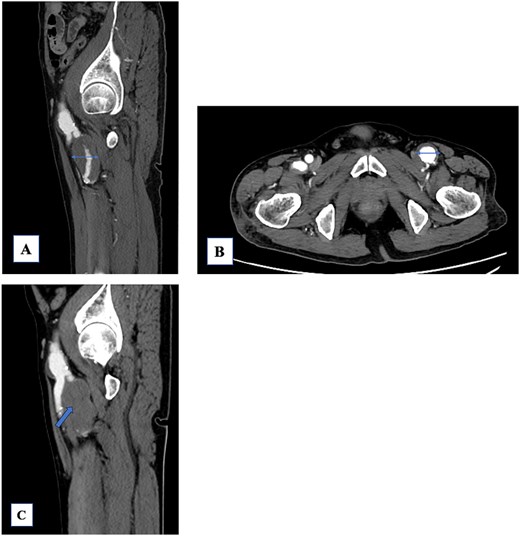

A 74-year-old man with known bilateral PFAAs (left: 32 mm; right: 38 mm) and a left common femoral artery (CFA) aneurysm (CFAA) (28 mm) (Fig. 1A and B) was referred to our department because of sudden-onset left thigh pain and inability to walk. Physical examination revealed left thigh swelling and livedo reticularis. Left popliteal and pedal pulses were palpable. Contrast-enhanced computed tomography (CT) demonstrated acute thromboembolism within the left PFAA, with complete distal PFA occlusion; the left PFAA had enlarged to 35 mm, and a thrombus was present within the left superficial femoral artery (SFA); however, the distal vessels showed contrast enhancement (Fig. 1C). ECG showed sinus rhythm. Echocardiography showed no intracardiac thrombus and preserved cardiac function. The ankle-brachial index was normal. Laboratory data revealed elevated creatine kinase levels (peak = 21 675 U/L) and a mild increase in the erythrocyte sedimentation rate, with otherwise normal renal function. After 5 days of systemic heparinization, elective surgery was performed under general anesthesia. We performed surgery to prevent recurrent SFA thrombosis and to avoid potential PFAA rupture. Surgery was deferred for 5 days because the pre-existing collateral circulation appeared well developed, allowing symptomatic improvement with systemic heparinization and preventing progression to thigh muscle necrosis. During this interval, the creatine kinase levels peaked and then dropped, accompanied by thigh pain relief and recovery of ambulation. Subsequently, the patient underwent aneurysm resection under stable hemodynamic and metabolic conditions. A 15-cm longitudinal incision was made in the left inguinal region. The CFA, SFA, and PFA were exposed and several branches were ligated (Fig. 2A). A lateral circumflex femoral artery branch arising near the CFA bifurcation showed strong backflow; therefore, reconstruction of this branch was planned to preserve lateral thigh perfusion. The PFAA was opened, revealing a large organized thrombus with no backflow from the distal vessels. As reconstruction of the peripheral PFA was technically difficult, we performed complete PFAA resection and replaced the CFAA with an 8-mm straight prosthetic graft (Intergard K; Cosmotec, Tokyo, Japan). A lateral circumflex femoral artery branch was anastomosed to the prosthetic graft (Fig. 2B). The postoperative course was uneventful, and the patient regained independent ambulation. Contrast-enhanced CT confirmed satisfactory perfusion (Fig. 3A and B). The patient was discharged on postoperative Day 14.

(A) The left profunda femoris artery aneurysm (PFAA) measures 32 mm. A large thrombus is observed. The peripheral vessels are patent. (B) The common femoral artery aneurysm (28 mm) shows a mural thrombus, and the left PFAA is enlarged to 35 mm. (C) The PFAA is completely occluded by the thrombus.